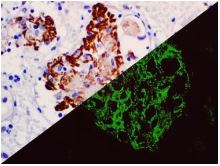

Bio SB has developed a highly sensitive Immunofluorescence and non-biotin monovalent Fab micropolymer IHC detection systems for the detection of IVD antibodies for Complement (C1q, C3c, C3d, C4c, C4d), Serum Proteins (Albumin and Fibrinogen) and Immunoglobulins (IgA, IgD, IgE, IgG, IgM, Kappa and Lambda) related to autoimmune conditions. Our innovative IF and IHC detection systems and high affinity antibodies, have opened the doors for a faster and accurate Immunofluorescence and Immunohistochemistry applicable to Autoimmune Disease like Nephropathies and Lupus.

These antibodies and detection systems are intended for use in Immunohistochemical (IHC) and Immunofluorescence (IF) applications of formalin-fixed paraffin-embedded tissues (FFPE), frozen tissue sections and cell preparations.